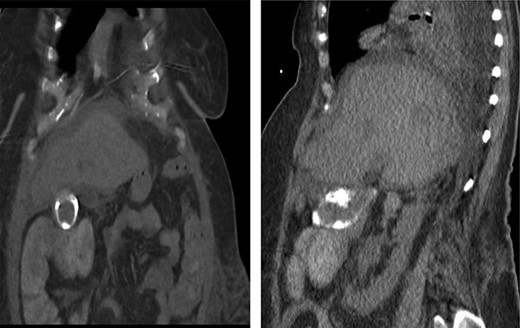

A 70-year-old female with congestive heart failure, atrial fibrillation, and end-stage renal disease presented to the general surgery clinic with a radiographic finding of a CCF. During workup for upper gastrointestinal bleeding, a computed tomography (CT) enterography incidentally demonstrated a fistulous connection between her gallbladder and the proximal transverse colon (Fig. 1). In the clinic, she reported right upper back pain that was unrelated to meals. She had no abdominal tenderness and her liver function tests were within normal limits.

Preoperative CT enterography demonstrating a CCF; (a) coronal view and (b) sagittal view, the white arrow indicates the location of the fistula.

In this study, we were able to track the evolution of the patient’s cholecystoenteric fistulae. She was managed by the same surgeon over the 5 years from her initial episode of cholangitis to her eventual cholecystectomy. The initial CT scan taken during her hospitalization shows an inflamed gallbladder abutting the proximal transverse colon (Fig. 2). The CT enterography obtained 5 years later depicts a fistula that developed in this same region (coronal and sagittal views, Fig. 1). Intraoperatively, the fistula was also found at this location. It is difficult to ascertain when the fistula developed as the patient may have been asymptomatic for years.